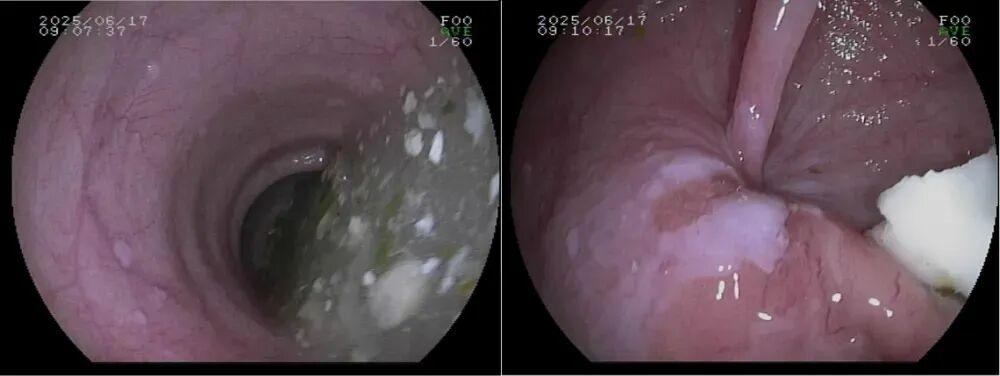

診斷賁門失弛緩症和排除腫瘤的“偵察兵”,食管可能明顯變粗(擴張),嚴重時像被撐大的水管,甚至出現彎曲扭曲,不像正常食管那樣筆直通暢。

其次,擴張的食管裏常殘留食物殘渣和黏液,黏膜被長期浸泡得發紅水腫。最關鍵的是賁門,醫生把胃鏡往胃裏送時,會明顯感覺這裏阻力很大,像推一扇鏽死的門——正常賁門碰到胃鏡會自然放鬆,這裏卻僵着,得突破阻力才能慢慢通過。

不過和腫瘤不同,賁門和食管的黏膜表面一般沒有潰瘍、腫塊這些異常凸起,主要問題是“門打不開”和“通道變形”,不是“長了壞東西”。

胃鏡:食管扭曲擴張、食物殘渣和黏液瀦留,賁門緊閉,胃鏡通過阻力明顯。